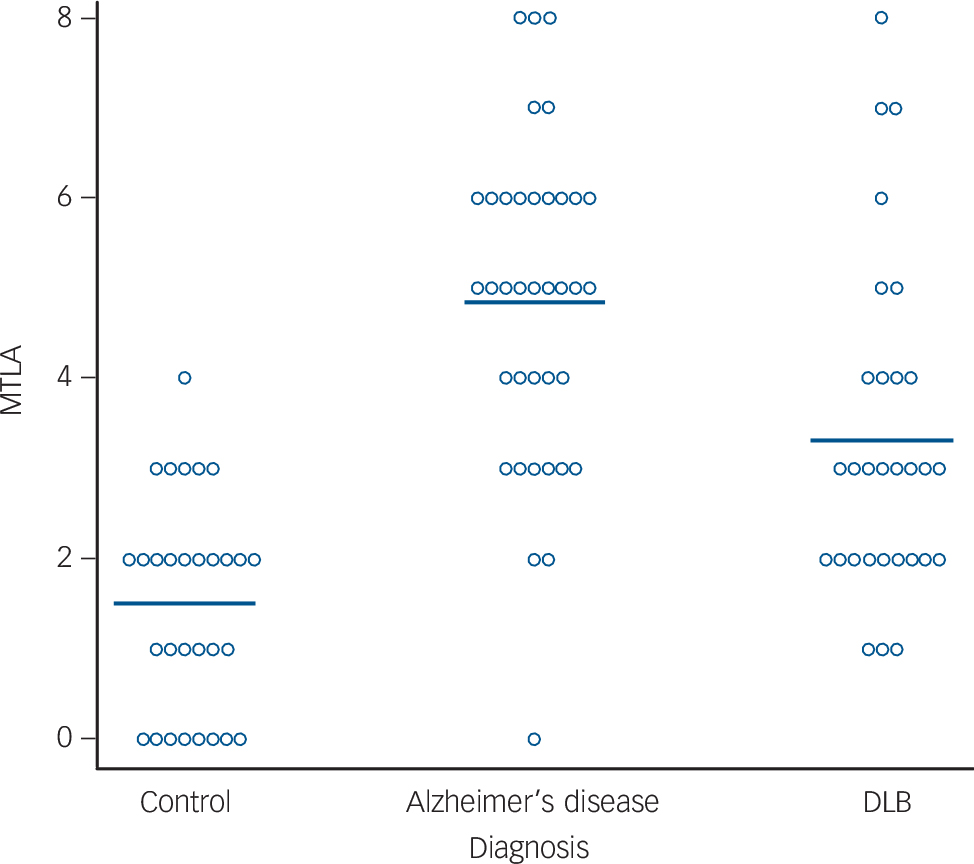

Figure 1 shows typical CT scans, and Fig. 2 shows the MTLA rating scores by group. In our previous examination of MTLA, we found that a cut-off of ⩾5 optimally distinguished Alzheimer's disease from DLB and vascular dementia. Reference Burton, Barber, Mukaetova-Ladinska, Robson, Perry and Jaros7 With this cut-off, none of the control participants, 6/30 DLB, and 23/37 Alzheimer's disease, had marked MTLA. So a high MTLA score was a good test for excluding non-dementia and most DLB cases, with a positive predictive value of 79%, but a lower sensitivity (62%) for detecting all Alzheimer's disease cases.

Fig. 2 Medial temporal lobe atrophy rating (L+R) for all participants. Horizontal bar shows group means. DLB, dementia with Lewy bodies; MTLA, medial temporal lobe atrophy.